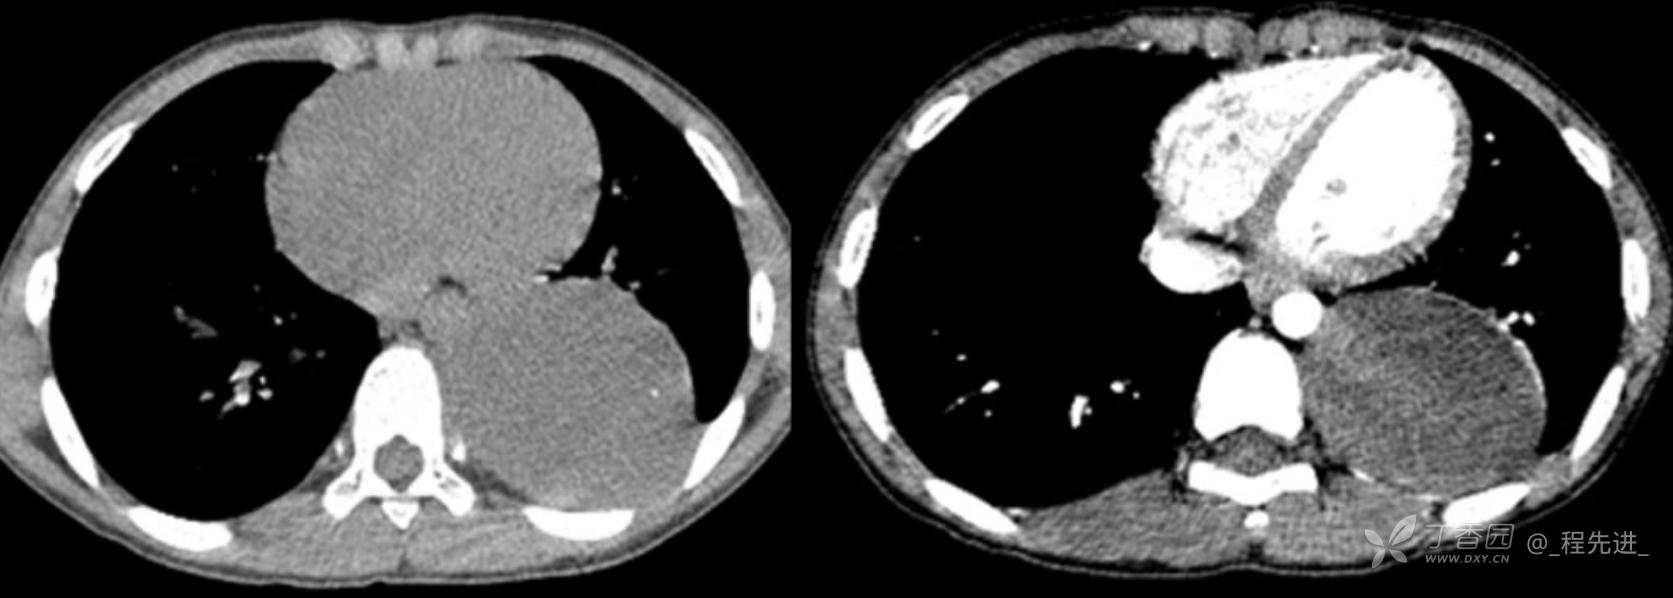

11月特别精彩病例|胸片示“左侧胸腔包裹性积液”,CT增强你诊断啥?【病理已公布】

呱呱叫了 等 3 位达人已点赞男,11岁,患儿因其爷爷近期在我院诊断“肺结核”,于外院行结核筛查,胸片示“左侧胸腔包裹性积液”,近期无咳嗽、发热、纳差、盗汗、乏力、胸痛、胸闷、气促不适,精神反应可,为求明确“左侧胸腔包裹性积液”病因,遂来我院门诊就诊,门诊以“胸腔积液查因”收住入院。发病以来,精神尚可食欲如常,大便如常,小便量如常,体重无明显变化